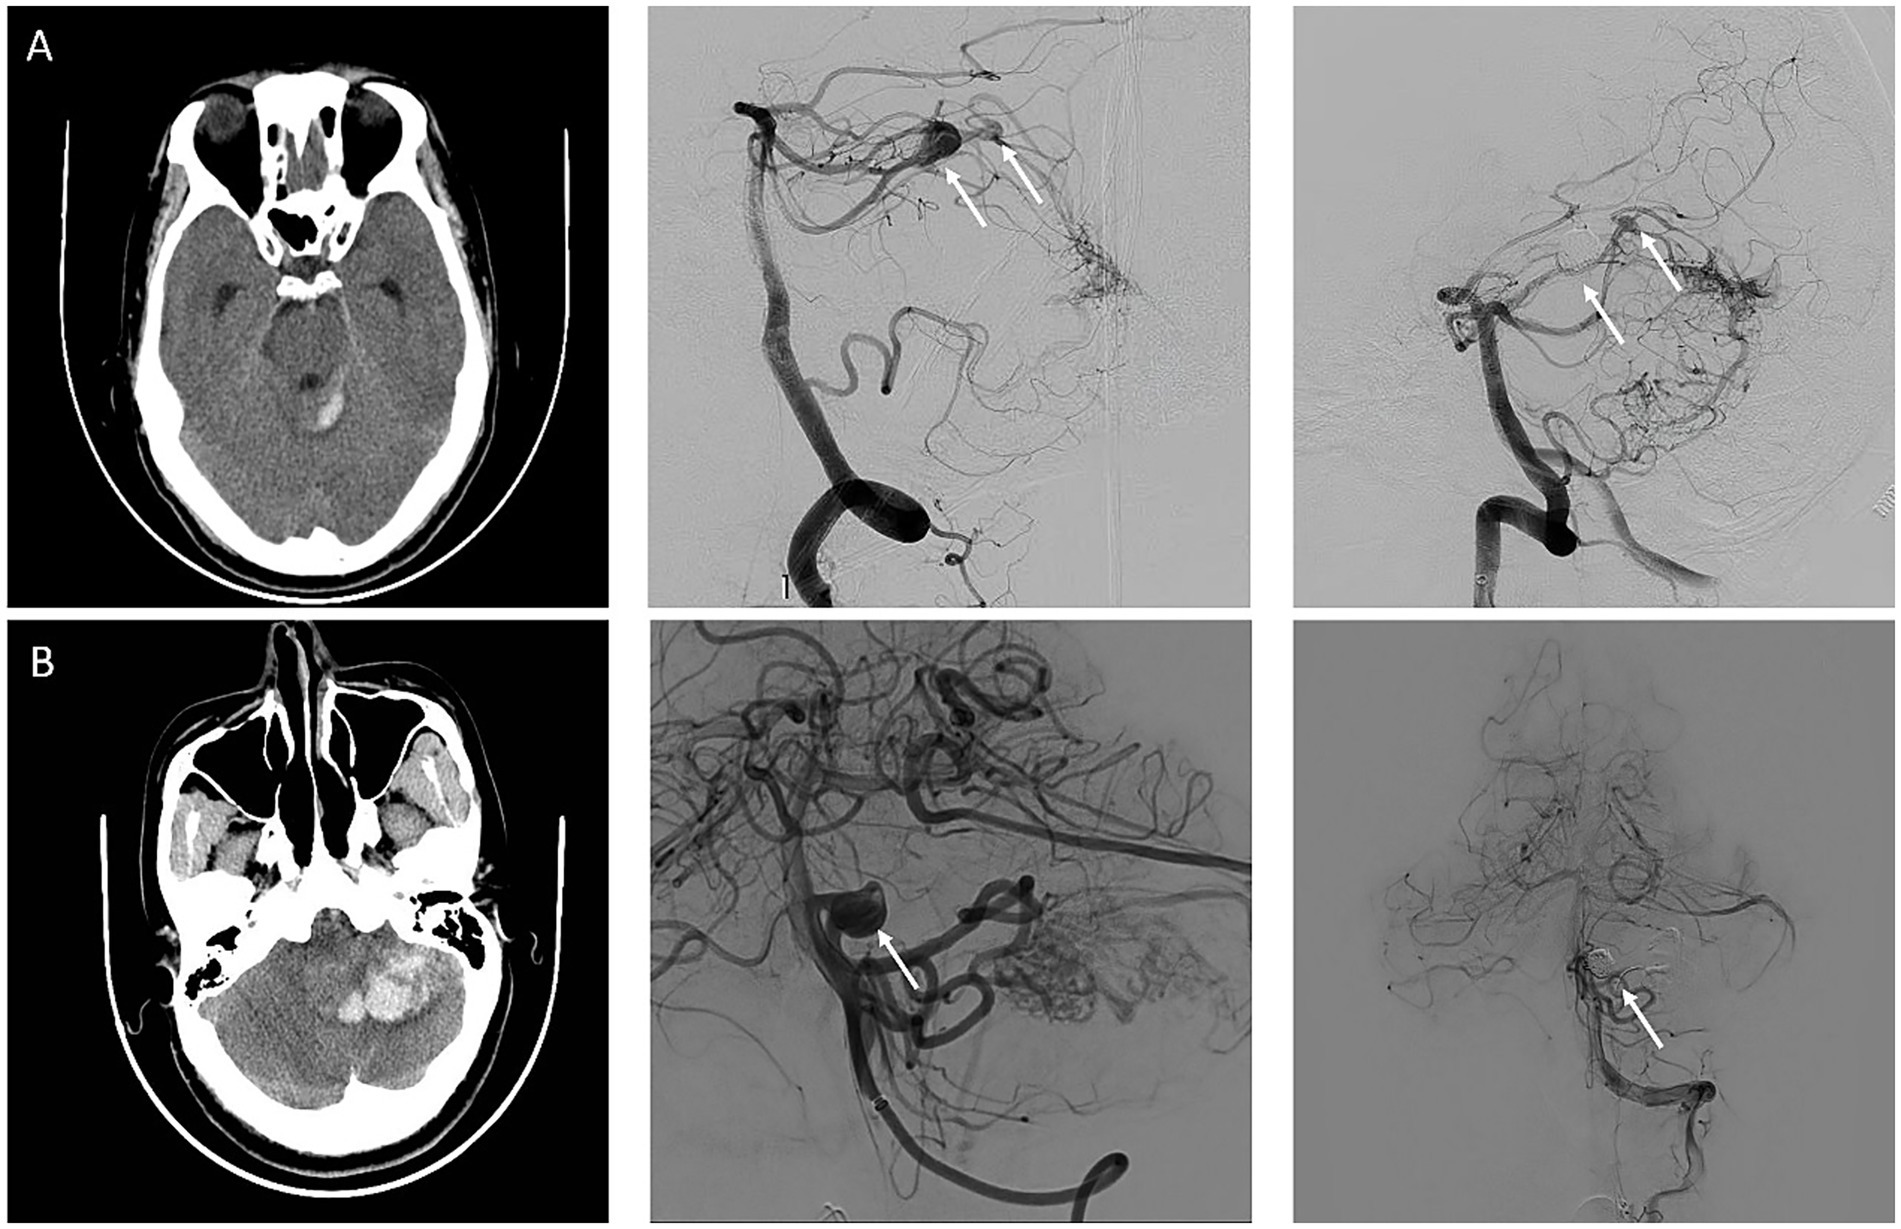

Background: Flow-related aneurysms (FA) is more common and of higher rupture risk in posterior circulation arteriovenous malformations (pAVM). However, risk factors for FA rupture in pAVMs are understudied and warrant further investigation. Objective: To investigate risk factors for FA rupture associated with pAVMs using multi-centric database from January 1 2020 to December 31 2024. Methods: Patients diagnosed with AVM were selected from databases. Patients with ruptured FAs and those with unruptured FAs were compared. Independent student's t-test, Mann-Whitney U test, Fisher's exact test and multivariable binary logistic regression were used to analyze. Results: Among 284 patients, 37 patients with 22 ruptured FAs and 28 unruptured FAs met the inclusion criteria. Ruptured FAs Ruptured FA are associated with located in smaller pAVMs (2.41 ± 1.02 cm vs 3.93 ± 2.68 cm, P = 0.001) and Spetzler–Martin grading I to II (P = 0.013). Patients with ruptured FAs had greater aneurysm size (median size, 4.55 mm [IQR, 3.20-7.55 mm] vs 3.00 mm [IQR, 2.40-5.00 mm]; P = 0.009), larger size ratio (median, 2.72 [IQR, 1.95-4.12] vs 2.23 [1.10-2.87]; P = 0.021) and larger relative size ratio (median, 0.24 [IQR, 0.137-0.358] vs 0.096 [IQR, 0.063-0.129]; P < 0.001) compared to unruptured ones. Only AVM size (OR, 0.92 [95%CI, 0.84-0.99]; P = 0.039) and size ratio (OR, 1.66 [95%CI, 1.07-2.59]; P = 0.024) remained associated with the risk of rupture in multivariable binary logistic regression. Conclusion: Size of pAVM and size ratio of FA to average parent vessel diameter are independent risk factors of FA rupture associated with pAVM.